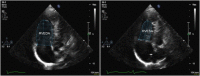

In the neonatal and pediatric intensive care setting, bedside cardiac ultrasound is often used to assess ventricular dimensions and function. Depending upon the underlying disease process, it is necessary to be able to evaluate the systolic and diastolic function of left and or right ventricles. The systolic function of left ventricle is mostly assessed qualitatively on visual inspection "eye-balling" and quantitatively by measuring circumferential fraction shortening or calculating the ejection fraction by Simpson's planimetry. The assessment of left ventricular diastolic function relies essentially on the mitral valve and pulmonary venous Doppler tracings or tissue Doppler evaluation. The right ventricular particular shape and anatomical position does not permit to use the same parameters for measuring systolic function as is used for the LV. Tricuspid annular plane systolic excursion (TAPSE) and S' velocity on tissue Doppler imaging are more often used for quantitative assessment of right ventricle systolic function. Several parameters proposed to assess right ventricle systolic function such as fractional area change, 3D echocardiography, speckle tracking, and strain rate are being researched and normal values for children are being established. Diastolic function of right ventricle is evaluated by tricuspid valve and hepatic venous Doppler tracings or on tissue Doppler evaluation. The normal values for children are pretty similar to adults while normal values for the neonates, especially preterm infants, may differ significantly from adult population. The normal values for most of the parameters used to assess cardiac function in term neonates and children have now been established.